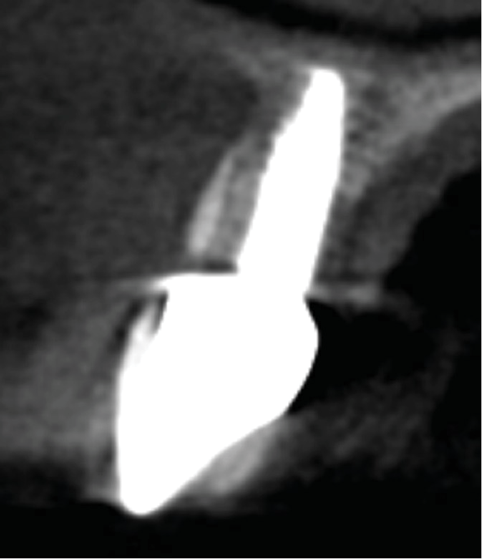

Fig 3. Initial diagnostic CBCT.

Figure 3

Fig 4. Diagnostics measurements include alveolar bone height, root length in the bone, and distance from the gingival margin to the buccal bone level.

Figure 4